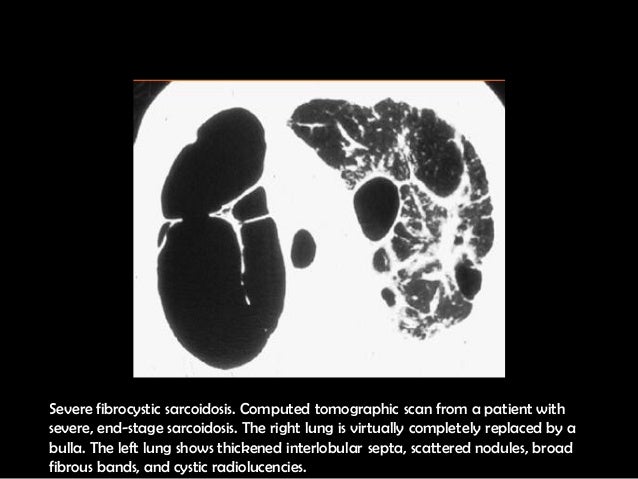

Sarcoidosis

via

www.slideshare.net

es.slideshare.net